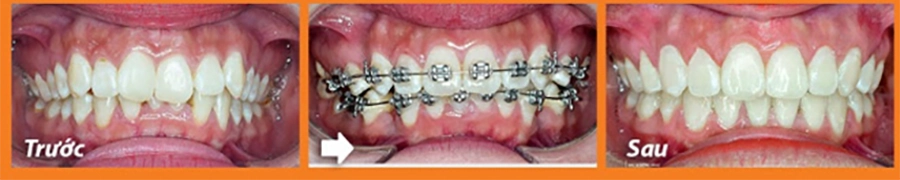

2.1 Cải thiện thẩm mỹ khuôn mặt và nụ cười

Một trong những lợi ích rõ ràng nhất của niềng răng là mang lại hàm răng đều đặn, giúp nụ cười trở nên hài hòa và cuốn hút hơn. Khi răng được sắp xếp đúng vị trí, khuôn mặt cũng trở nên cân đối, đặc biệt là ở vùng miệng và cằm.

Nhiều trường hợp răng hô, móm hoặc khấp khểnh không chỉ gây mất tự tin mà còn khiến khuôn mặt mất cân xứng. Sau khi chỉnh nha, gương mặt trở nên hài hòa hơn, nụ cười tự nhiên và thoải mái hơn.